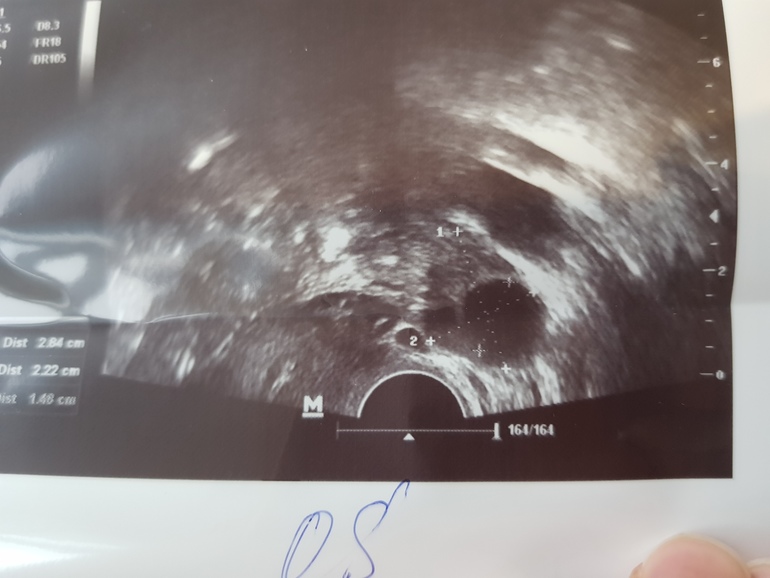

На 9й дц доминантный фолик 15мм, но он с левой стороны, там непроходима труба, так что пролет.

Эндик подвел, всего 4,7мм, это тоже к пролету. Справа мелкие фолики до 5мм, яичник уснул. До этого ходила пол года на фолликулометрию и работал правый я, а теперь вот стимуляция левый разбудила.

Левый: